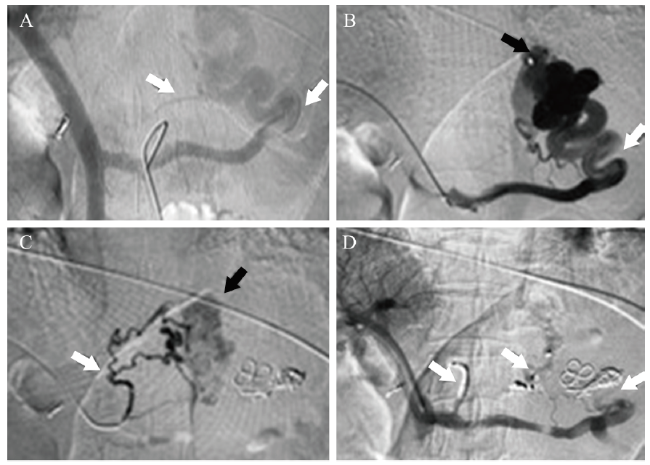

图1 间接门静脉造影+经皮经肝穿刺门静脉造影+胃冠状静脉及食管胃底曲张静脉栓塞术

注:该例为54岁男性患者, 有乙型肝炎后肝硬化病史, A为导管/导丝配合下经股动脉入路超选入肠系膜上动脉行延迟造影(间接门静脉造影), 可见门静脉、肠系膜上静脉及两支异常增粗的胃冠状静脉及食管胃底静脉(白箭头);B为经皮经肝穿刺门静脉造影, 进一步证实迂曲扩张的胃冠状静脉及食管胃底静脉(白箭头), 曲张静脉周边可见造影剂溢出征象(黑箭头);C为调整导管选入近门静脉主干处曲张静脉, 并应用微导管超选入曲张静脉造影, 可见迂曲增粗胃底静脉(白箭头), 周边可见造影剂溢出征象(黑箭头);D为曲张静脉栓塞治疗后复查门静脉造影, 可见曲张静脉血流截断, 未见显影, 周围异常染色消失, 栓塞满意(白箭头)。